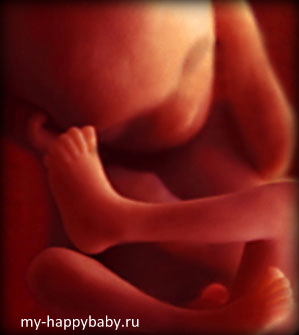

17 Тиждень вагітності

17 акушерська тиждень вагітності - це початок 5 місяці вагітності. Вага малюка починає помітно зростати. Ви вже відчули перші ворушіння або ж зовсім скоро відбудеться цей хвилюючий і такий довгоочікуваний момент!

Малюк стрімко зростає. Його вага близько 140 грамів, а зріст приблизно 14 см. 90 відсотків ваги малюка складає вода!

Що нового відбулося за цей тиждень з вашим малюком?

- починає утворюватися підшкірно-жирова клітковина (жировий прошарок). Вона бере участь у виробленні енергії, важливий для здійснення теплообміну. Шкіра малюка вже має чотиришарове будова.

- імунна, центральна нервова і ендокринна системи почали свою роботу

- наднирники виробляють необхідні гормони, їх будова вдосконалюється

- гіпофіз почав повноцінно функціонувати

- збільшується обсяг головного мозку, на поверхні кори головного мозку є перші борозни і звивини

- очі повністю сформовані. Вони здатні відрізняти темряву від світла.

- повністю сформувалися слухові кісточки, що знаходяться в середньому вусі. Дитина починає чути!

- кістки стають ще міцнішими, а зачатки молочних зубів покриваються твердою кістковою тканиною (дентином)

- повністю сформована плацента (товщина - приблизно 2,5 см, вага - приблизно 480 грам)

Що вміє малюк?

- на 17 тижні вагітності малюк починає чути! на різні звуки він реагує по-різному. Спершу він загострює увагу на тих звуках, які складають його світ: биття маминого серця, його ритм, рух по венах крові. Потім малюк починає вловлювати ті звуки, які надходить ззовні. Вчені впевнені, що малюк дізнається голос мами відразу після свого народження.

- він активно рухає ручками, підносить їх до обличчя, махає, випрямляє і згинає, розгинає і згинає свої ніжки. Його рухи стали більш скоординованими. Можливо, ви вже відчули ці рухи.